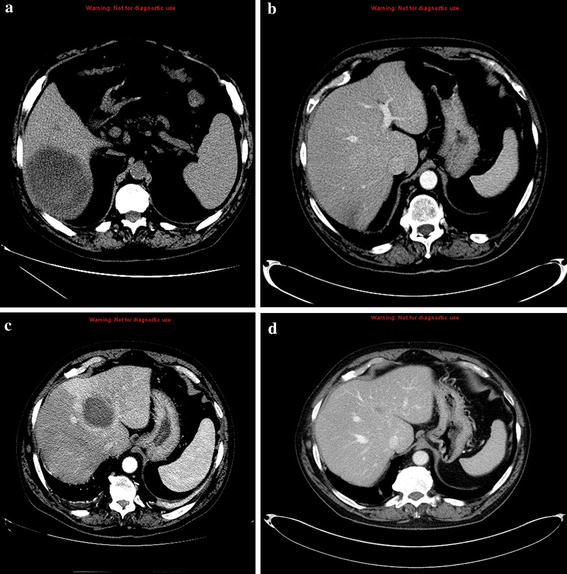

Hepatic amebiasis, 5 weeks of pregnancy. a Inhomogeneous mainly The Medical Record Indicates Hepatic Amebiasis Quizlet amebiasis occurs worldwide but is most common in the tropics, subtropics, and other areas with poor sanitation and health. amebic liver abscess is the most common extraintestinal manifestation of amebiasis. important diagnostic steps include stool analysis and liver ultrasound to assess extraintestinal amebiasis. Men between the ages of. study with quizlet and memorize flashcards containing terms. The Medical Record Indicates Hepatic Amebiasis Quizlet.